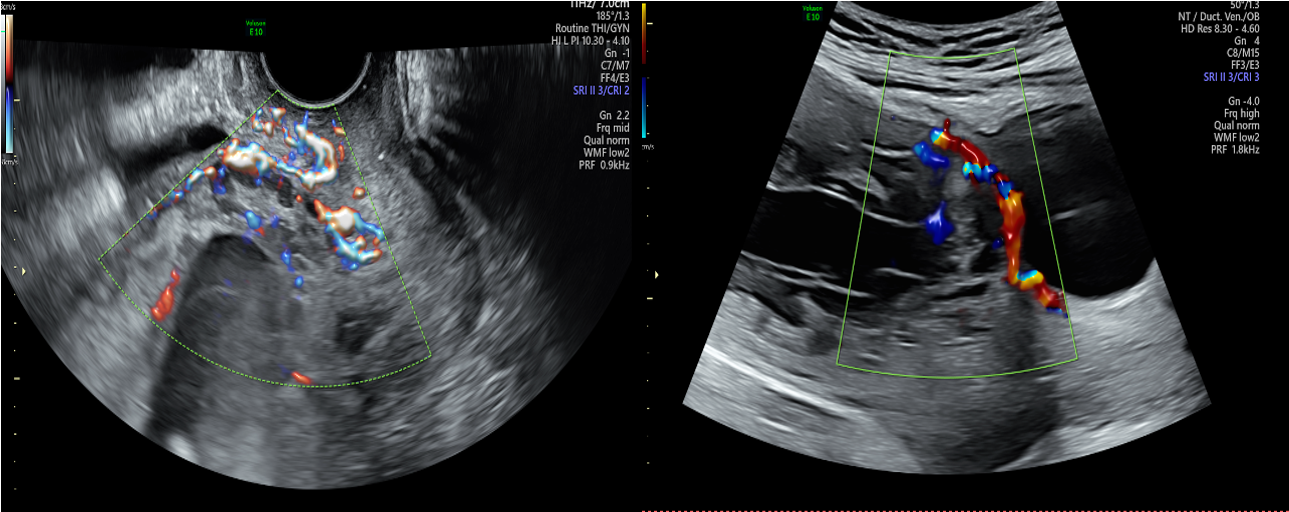

小彭在孕32+5周时,外院磁共振检查却提示未见胎盘植入,但B超始终提示胎盘内见数个液性回声,前壁峡部肌层内血流信号丰富,磁共振与超声的检查结果似乎不一致,患者及家属辗转苏州多家医院咨询相关风险,一路奔波,最后来到我院找到妇产科张跃明主任。张主任仔细阅读磁共振片子(图2),发现胎盘虽未完全覆盖宫颈内口,但整个胎盘位于子宫下段前壁及前次剖宫产疤痕处,子宫下段前壁肌层缺如,认为此例凶险性前置胎盘情况不可小觑。随后通过B超检查行胎盘植入评分为5分(≤5分为轻度),如果按胎盘植入分判断,可期待至37周终止妊娠即可,所需输血量较少,且无需其他学科参加。但张跃明主任凭借多年丰富的临床经验,结合磁共振图像及B超评价,认为情况远不如看上去一般轻松。目前产妇已孕36+4周,不能继续再期待,应立即收入院。

图2